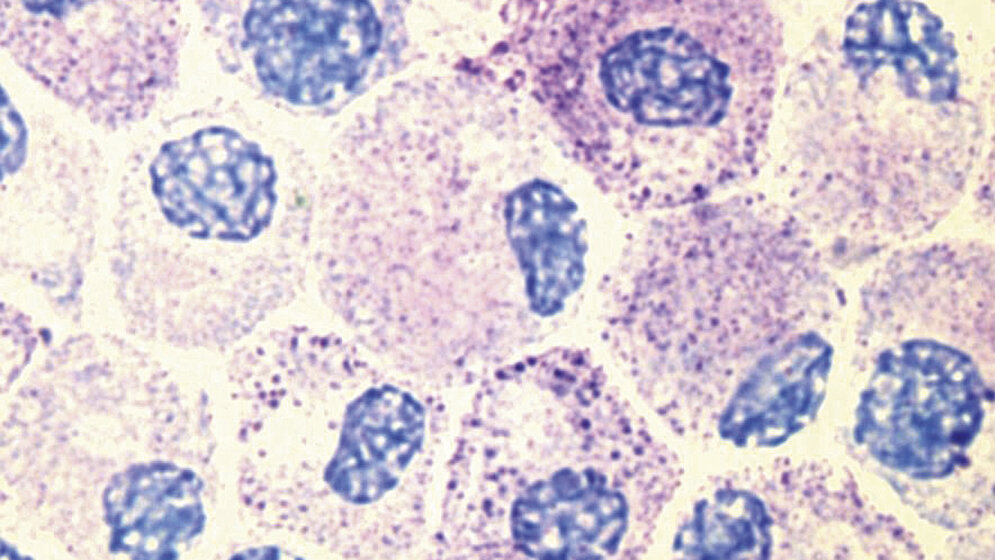

Das Mastzellaktivierungssyndrom (MCAS) ist eine häufig auftretende, selten erkannte Multisystemerkrankung, bei der es zu einer vermehrten Degranulation und damit zur Ausschüttung der Mastzellmediatoren aus den Mastzellen in den Körper kommt. Bei Betroffenen des MCAS können allergieähnliche Symptome, die bis zur Anaphylaxie reichen, bereits durch kleinste Umweltfaktoren ausgelöst werden. Im Gegensatz zur Mastozytose existieren für die MCAS keine klaren Diagnostikkriterien, und häufig sind sämtliche Marker im Blut negativ. Ausschlaggebend ist das klinische Erscheinungsbild, welches zu erkennen selbst langjährige Spezialisten vor eine große Herausforderung stellt. In den letzten Jahren wurden immer mehr Verbindungen zwischen MCAS und anderen komplexen Krankheitsbildern hergestellt, wie dem Ehlers-Danlos-Syndrom, der Fibromyalgie, der interstitiellen Cystitis und vielen mehr. Die genaue Ursache bleibt bislang unbekannt. Die MCAS kann nicht geheilt, aber symptomatisch therapiert werden. Hierzu sind häufig eine Kombination aus Medikamenten, eine Umstellung der Lebens- und Ernährungsweise und die Vermeidung von bekannten Auslösern nötig.